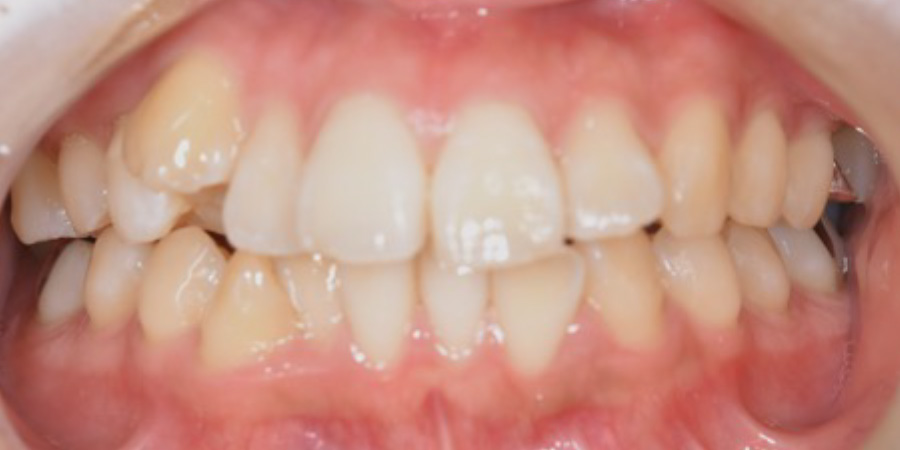

左側の顎がかくかくする

【マウスピース矯正】

- 左側の顎がかくかくする

- 1年3か月

- マウスピース矯正

980,000円(税込)

- 目立ちにくいマウスピース矯正(非抜歯矯正)

歯と歯の間に隙間をつくることにより、歯列弓を広げながら治療を行いました。

- ・後戻りする可能性があるのでリテーナーを最低でも矯正期間以上はつけること

・稀にほっぺた、唇、舌などに口内炎や傷ができることがあります